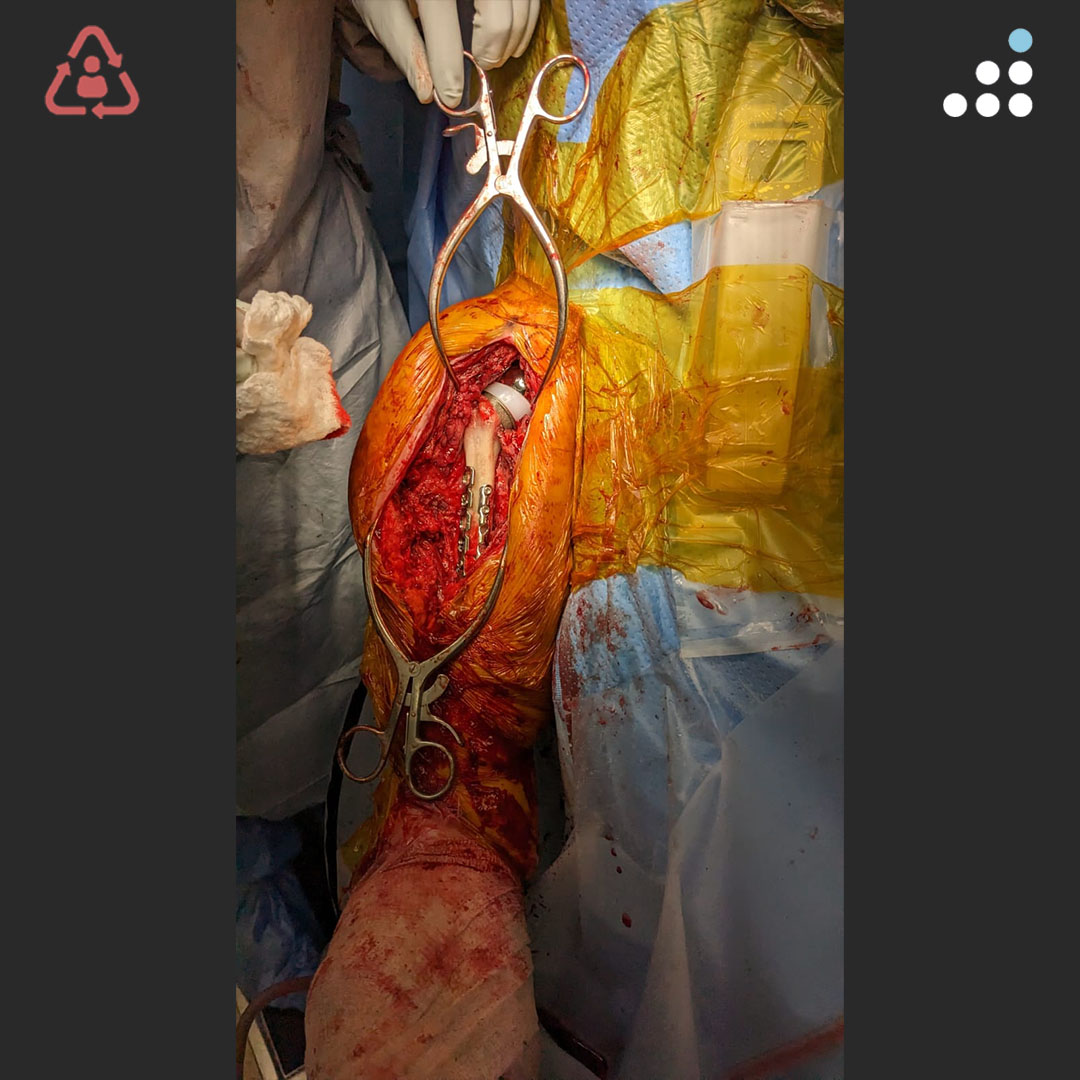

@orthobullets If there is still some cartilage left on the reverse Hill Sachs I’ve had some luck with doing a humeral head osteoplasty. I’ll use allograft chips or cement to backfill the defect after I tamp up articular surface and then try to get everything repaired especially in young pts